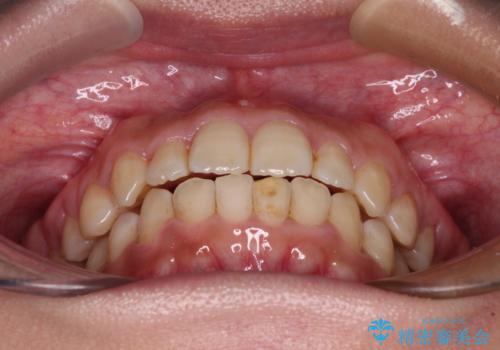

前歯のクロスバイト 目立たないワイヤー装置で速やかに矯正治療

- 前歯のクロスバイトを気にして来院された患者様です。

治療方法としては、マウスピース矯正(インビザライン)でもワイヤー矯正でも、何でも対応可能ですが、自己管理の煩わしさがなく、治療期間の目処を立てやすい表側のワイヤー矯正にて治療を行うこととしました。